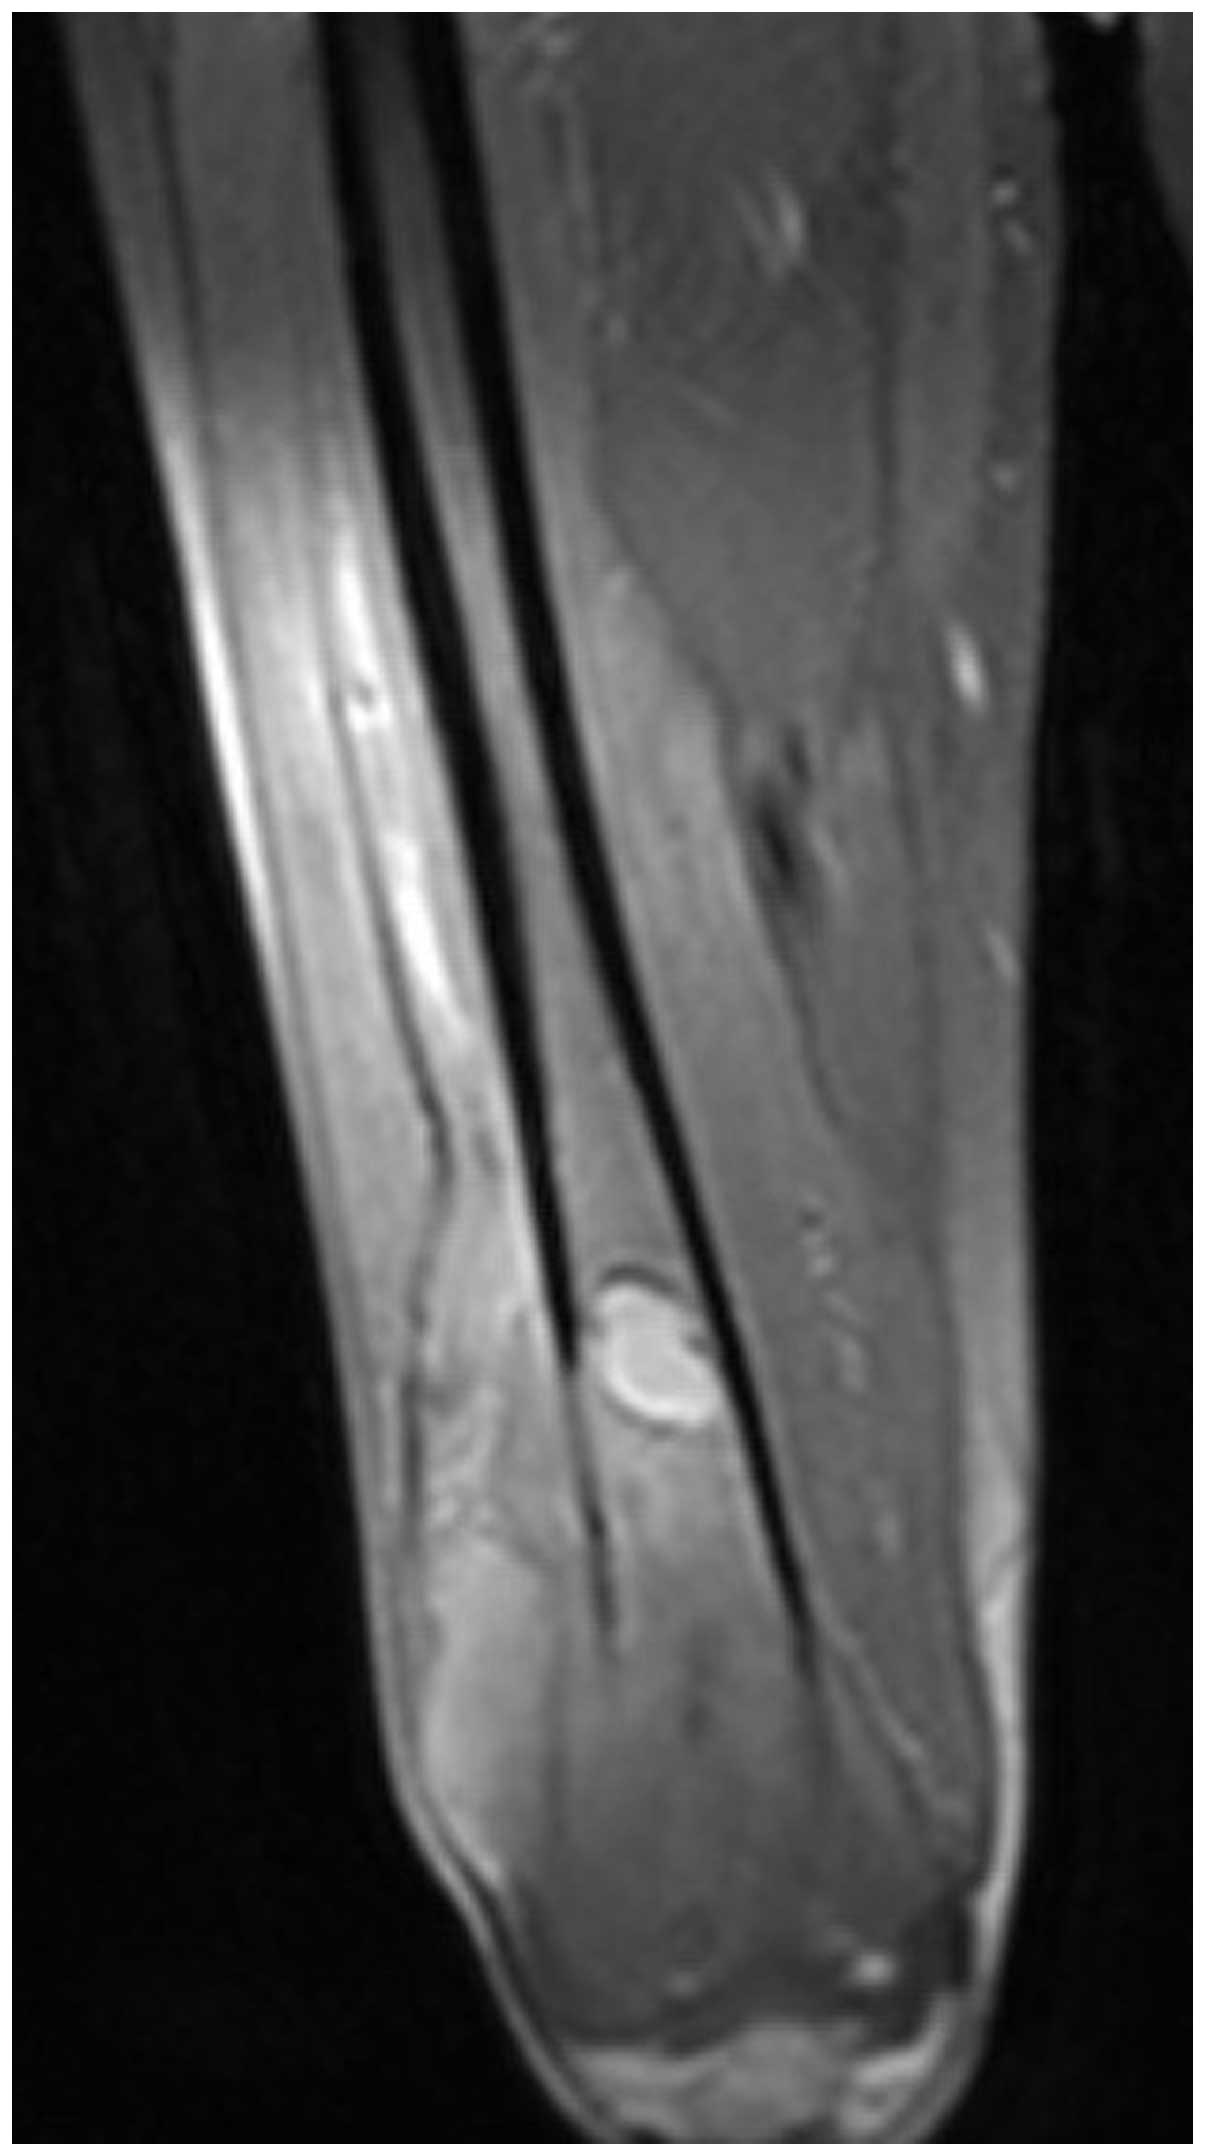

(Fig. 1). Magnetic resonance

imaging demonstrated an expansile, intramedullary, poorly defined

neoplasm with a moderately high signal intensity area on T1- and

T2-weighted images in the distal part of the femur, with diffuse

erosion of the cortex and involvement of the surrounding soft

tissue (Fig. 2). The intraosseous

central location and uniform cortical destruction indicated that

the lesion was not a soft-tissue sarcoma, which are associated with